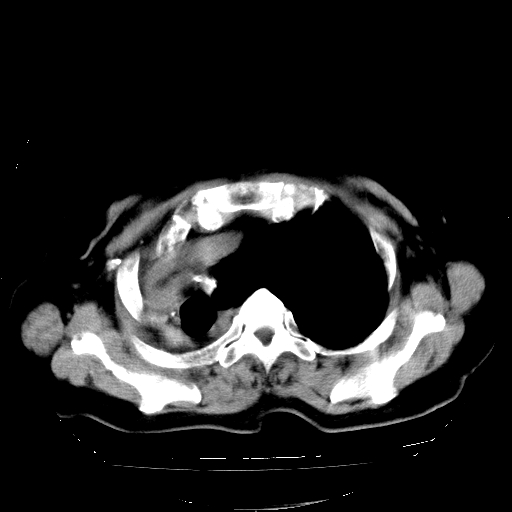

标题: CT23991:女,72岁,咳嗽、憋气一周。 [打印本页]

女,72岁,咳嗽、憋气一周,十年前曾患肺结核及胸膜结核。

右侧毁损肺,右侧纵隔疝

右侧毁损肺,右侧纵隔疝,左肺代偿!

1.右侧损毁肺伴胸膜钙化,2.左肺小结节灶,良性可能大,注意复查。3.肝脏左叶囊肿。4.先天性一侧肺不发育待出外(右侧胸廓无明显塌陷)。对比原片应该非常有帮助。

右侧肺毁损,左肺代偿性肺气肿,纵隔疝。